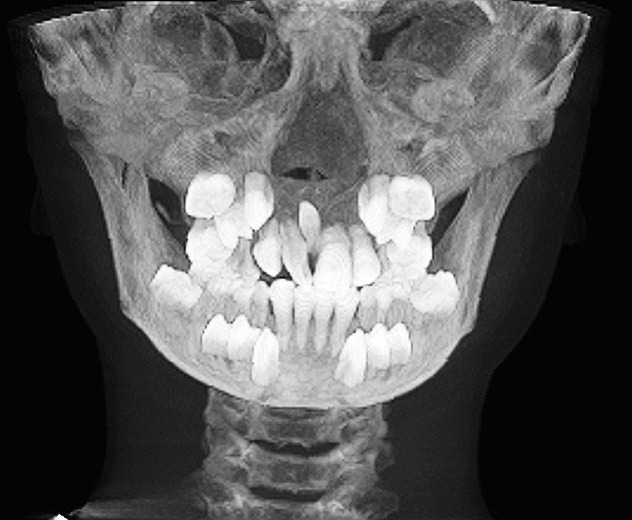

CTを取りました

顎骨のほぼほぼ中央に存在しています